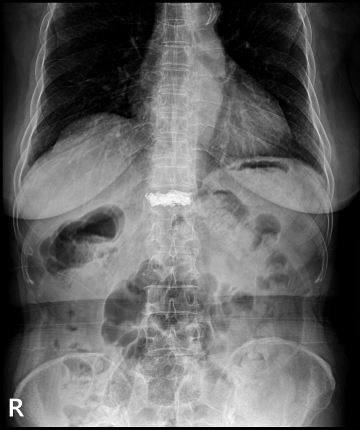

척추체 성형술 치료 방법

2022.12.21

2022.12.27

ㆍ환자 동의를 받은 자료이며, 이미지 사진은 실물과 다를 수 있습니다.

ㆍ모든 자료는 새움병원 자료입니다.